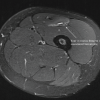

X-rays revealed cystic expansion and cortical thinning [3] of the proximal phalanges with lytic lesions (Fig. 2). Computed tomography imaging confirmed cortical destruction and periosteal reaction (Fig. 3).

Figure 3: Computed tomography radiographs.